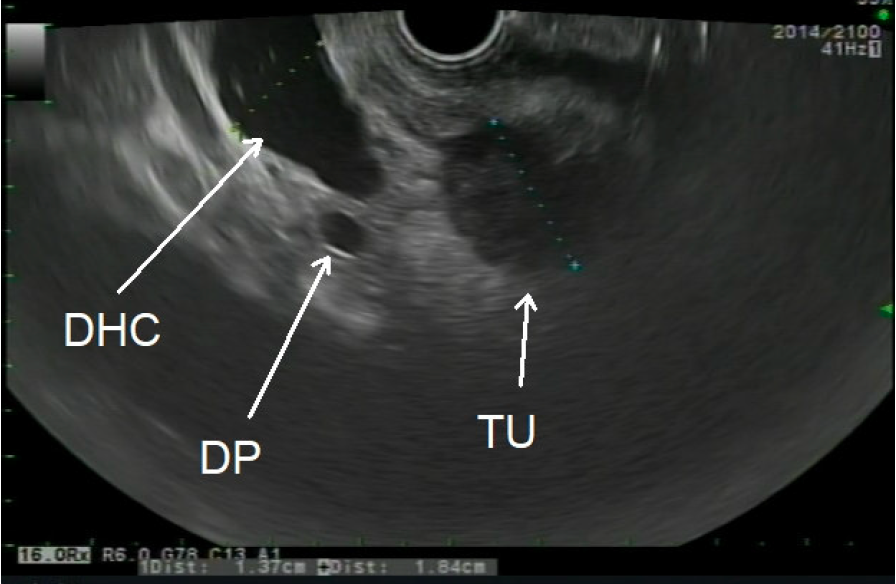

Wie funktioniert die EUS-FNB? Endosonographie: Ein Endoskop mit Ultraschallsonde wird durch den Mund oder den Darmausgang eingeführt, um hochauflösende Bilder der Organe im Bauchraum zu erzeugen. Zielgerichtete Biopsie: Eine dünne Nadel wird durch das Endoskop geführt und unter Ultraschallkontrolle gezielt in das verdächtige Gewebe platziert. Gewebeprobe entnehmen: Die Nadel entnimmt präzise Gewebeproben, die dann zur weiteren Untersuchung an ein Labor geschickt werden.